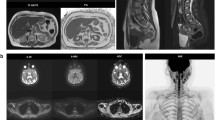

LFS is a rare, hereditary, autosomal dominant disorder, in which germline mutations lead to a functional inactivation of the TP53 tumour suppressor gene. As a result, the cumulative cancer incidence in subjects with LFS is markedly increased compared to the general population, reaching 50% in the third and fourth decade in females and males, respectively, while cancer prevalence approaches 100% in female subjects after the sixth decade [58]. Common malignant cancers in LFS include sarcoma, breast cancer, brain tumours, leukaemia, and adrenocortical carcinoma [20] (Fig. 3).

Case example. Images of a 29-year-old woman with Li-Fraumeni syndrome with prior history of giant cell fibroblastoma of the groin (13 years before), Paget disease of the right breast and grade-3 ductal intraepithelial neoplasia (DIN-3) of the right breast (8 years before). The patient underwent a first screening with WB-MRI, which revealed multiple abnormal findings. The high b-value maximum intensity projection displayed in lateral view with inverted grayscale (A) revealed three hyper-intense lesions in the pelvis. Firstly, a 8-cm mass highly suspicious for cancer was detected in the right gluteus (arrow in A and B), showing hyper intense appearance in high b-value images (top row, A and B), cystic areas in T2 weighted images (middle row, A and B) and irregular contrast enhancement in delayed post-contrast T1 weighted (W) Dixon images (bottom row, A and B). Secondly, a solid lesion with irregular shape was seen adjacent to the right femoral vessels (arrowhead in A and C), with hyper-intense appearance in high b-value images, heterogeneous signal in T2 W images and strong enhancement in post-contrast T1 W Dixon images (A and C, top, middle and bottom row, respectively). The finding was reported as strongly suspicious for local recurrence of fibroblastoma. Thirdly, an enlarged femoral lymph node was seen in the right thigh (dashed arrowhead in A). The patient underwent surgical resection of the suspicious lesion in the gluteus and dissection of the right groin, with histopathological diagnosis of high-grade sarcoma of the gluteus and local recurrence of fibroblastoma. Metastasis from high-grade sarcoma was diagnosed in the enlarged femoral lymph node. Two other focal lesions were detected, which were not visible in high b-value images (D and E, top row). In D, a solid, rounded lesion was seen the VII segment of the liver, with high signal intensity in T2 W images (D and E, middle row) and evidence of intralesional fat in the relative fat-fraction (rF%) map (D, bottom row). The lesion showed similar contrast enhancement compared to surrounding parenchyma in T1 W Dixon images (not shown). Although not suspicious for malignant cancer, the lesion was not visible in a prior MRI study; therefore, a percutaneous liver biopsy was performed, with benign findings suggestive of chronic inflammation, macrovescicular steatosis and ductal hyperplasia. Follow-up at seven months distance showed stable findings. In E, a lobulated bone lesion was seen in the right ilium, with minimal remodelling of the cortical bone and hyper-intense content in T2 W images (middle row), and intralesional fat content below 5% in the rF% map. The lesion was not visible in a prior MR study, and in the suspect of malignancy, a percutaneous biopsy was performed, which revealed sparse foci of epithelial tumoral cells, with immunohistochemical findings compatible with metastasis from occult breast cancer. Subsequent mammography and ultrasonography revealed no abnormal breast lesions and the patient is at present under strict follow-up